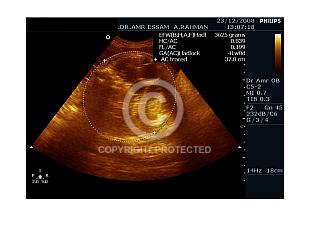

Fetal Hydronephrosis

625 views